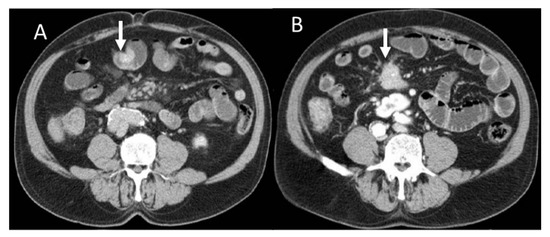

Neuroendocrine neoplasms (NENs) are a group of lesions originating from cells of the diffuse neuroendocrine system. NENs may involve different sites, including the gastrointestinal tract (GEP-NENs). The incidence and prevalence of GEP-NENs has been constantly rising thanks to the increased diagnostic power of imaging and immuno–histochemistry. Despite the plethora of biochemical markers and imaging techniques, the prognosis and therapeutic choice in GEP-NENs still represents a challenge, mainly due to the great heterogeneity in terms of tumor lesions and clinical behavior. The concept that biomedical images contain information about tissue heterogeneity and pathological processes invisible to the human eye is now well established. From this substrate comes the idea of radiomics. Computational analysis has achieved promising results in several oncological settings, and the use of radiomics in different types of GEP-NENs is growing in the field of research, yet with conflicting results. The aim of this narrative review is to provide a comprehensive update on the role of radiomics on GEP-NEN management, focusing on the main clinical aspects analyzed by most existing reports: predicting tumor grade, distinguishing NET from other tumors, and prognosis assessment.

Full article

Show Figures